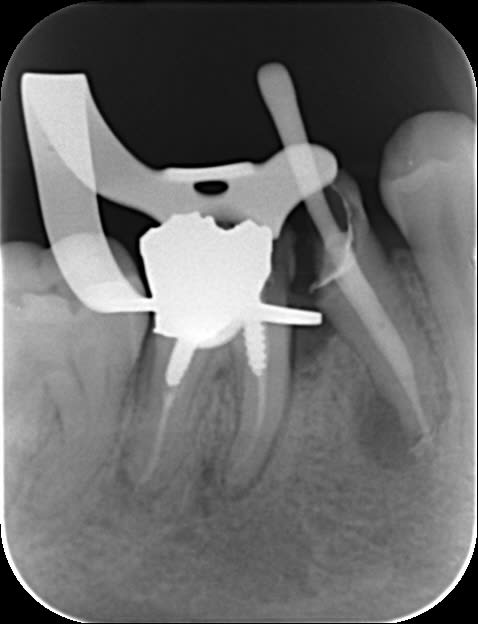

2 retraitements endo sur 45 46.

2 m85na9 - Eugenol

3 j2ewih - Eugenol

4 mbyxz8 - Eugenol

1 ojgvk3 - Eugenol